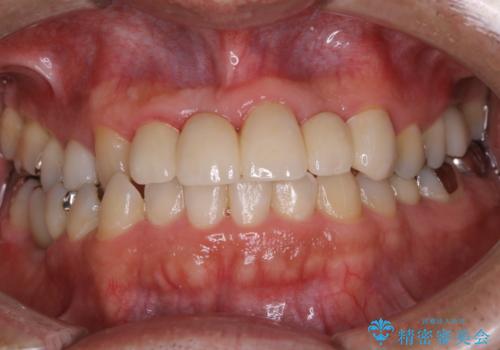

歯科衛生士によるPMTCでお口のケア

- 歯医者に来院することが久しぶりで、まずはクリーニングを希望とのことでした。コースや内容は、一番状態に合ったものでとのことだったため、PMTC60分コースを行いました。

PMTCとは「Professional Mechanical Tooth Cleaning」の略で、専用の機器を使った歯のクリーニングです。

審美的面だけではなく、歯周病や虫歯・口臭などのリスクを予防することができます。